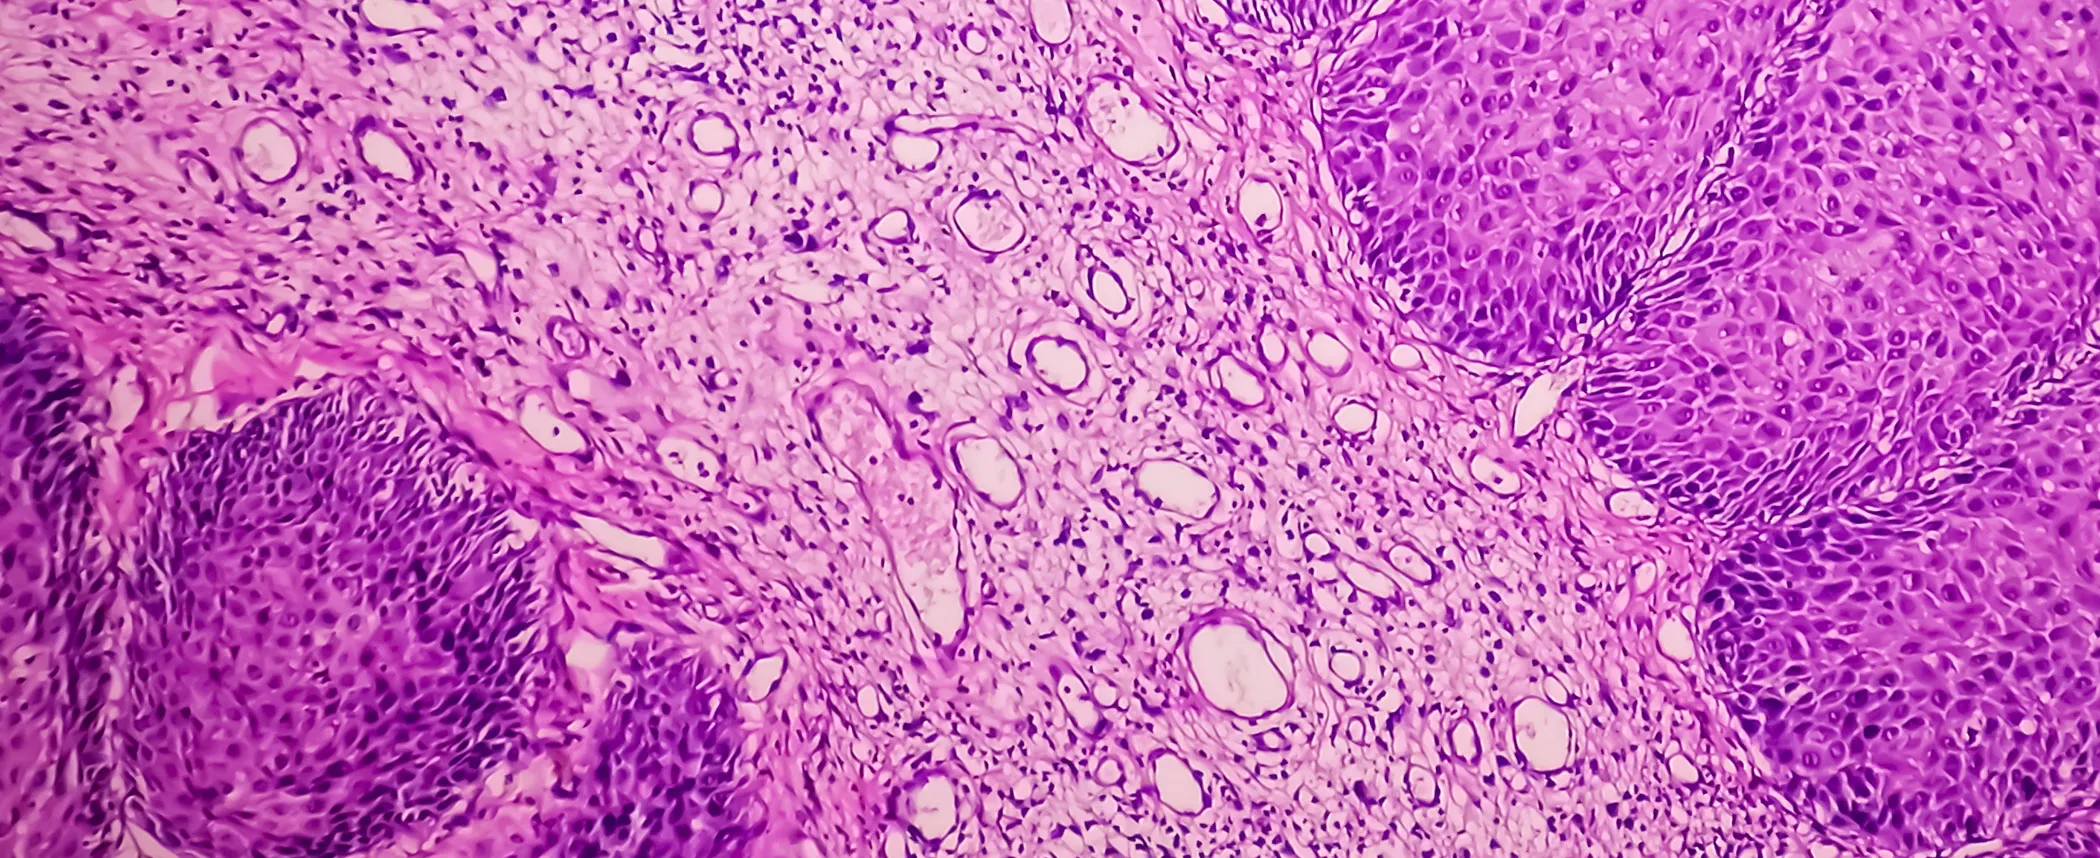

Dermatopatología de excelencia Ofrecemos diagnósticos precisos con sólida correlación clínico-patológica, orientados a respaldar mejor cada decisión médica.